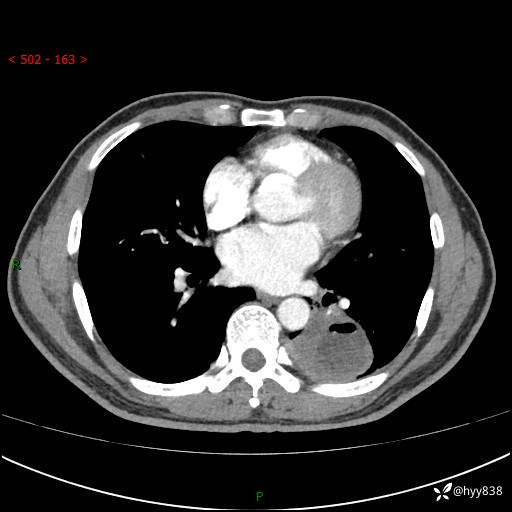

胸部CT平扫

增强